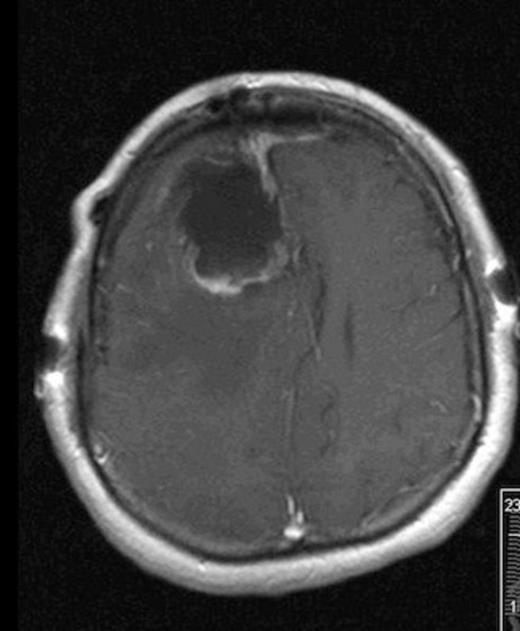

She was taken to the operating the following morning for a bicoronal craniotomy for a gross-total tumor resection with neuronavigation (Fig 2). Pathology was a dural-based WHO Grade 1 supratentorial haemangioblastoma. Microscopic findings demonstrated large vessels and abundant capillary networks, with a cellular proliferation of large stromal cells with clear vacuolated cytoplasm (Fig 3,4,5). There were significant hyperchromatic nuclei and multiple areas of PAS positive pinkish globules (Fig 3,4,5).

10 x Haematoxylin and Eosin stain showing typical microscopic pathology of capillaries and interstitium